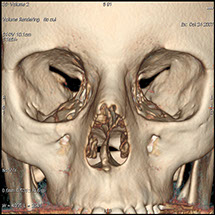

Le scanner comporte un lit d'examen, sur lequel le patient est allongé, qui va se déplacer lentement pendant l’examen et un anneau qui va tourner autour du patient en émettant des rayons X (il contient le tube à rayons X et les récepteurs). Les rayons X vont traverser la région à étudier et permettre d’obtenir des images en coupe de la zone à étudier. Des traitements de numérisation informatique permettront d'obtenir  des images 2D ou 3D dans différents plans et volumes.

Grâce aux scanners multidétecteurs (ou multi-barrettes) à acquisition spiralée, on obtient une exploration très précise d'un large volume du corps humain pour un temps d'acquisition de quelques dizaines de secondes.

C’est un élément majeur dans la panoplie radiologique. L’apport diagnostique du scanner est important notamment dans :

• Les pathologies ORL et du rachis (souvent également étudiées en IRM).